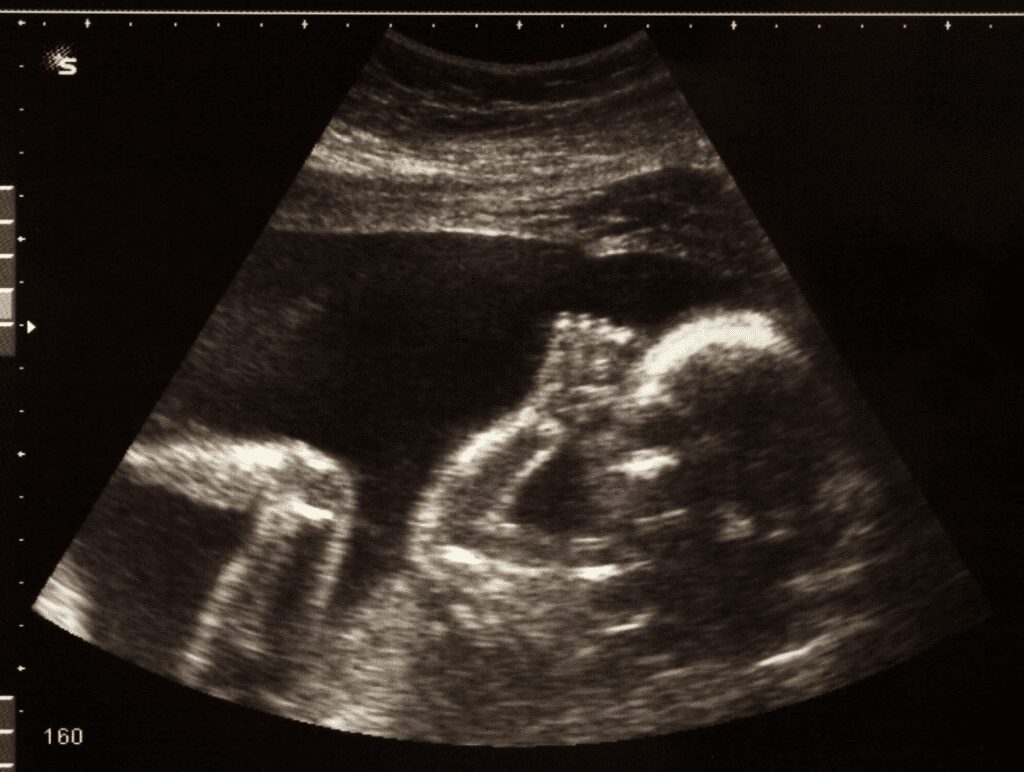

Baby Kenan was projected to have scoliosis, which doctors attributed to intrauterine growth restriction. At Rochelle’s 31-week prenatal imaging appointment, however, the ultrasound revealed new frightening details about Kenan’s health.

In addition to scoliosis, doctors detected curved long bones, a misshapen head, and leg growth that had not surpassed the second percentile.

According to scientific research, twin babies are highly active at 31 weeks, tracking light and developing all five senses. At 31 weeks, babies are kicking their feet and sucking their tiny thumbs.